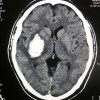

Identifikasi Penyebab

Panduan AAN 2023 menekankan bahwa klinisi harus memastikan bahwa pasien mengalami cedera otak yang fatal dan permanen akibat mekanisme yang diketahui dapat menyebabkan mati otak sebelum memulai evaluasi Jika pasien mengalami koma, apnea, dan kehilangan refleks batang otak tetapi tidak terdapat mekanisme cedera otak yang diketahui dapat menyebabkan mati otak, maka klinisi seharusnya tidak melakukan evaluasi. Selain itu, klinisi juga diharapkan memastikan bahwa hasil neuroimaging konsisten dengan mekanisme dan tingkat keparahan cedera otak.

Cedera otak yang dapat menyebabkan mati otak melibatkan berbagai faktor, seperti cedera otak traumatik, perdarahan subarachnoid, perdarahan intraserebral, stroke iskemik, tumor otak, cedera otak iskemik-hipoksik, ataupun infeksi intrakranial. Namun, perlu diingat bahwa terdapat kondisi yang memiliki gejala mirip mati otak tetapi bersifat reversible, seperti karsinomatosis leptomeningeal, gigitan ular, dan botulisme.[3]

Evaluasi Mati Otak pada Pasien dengan Cedera Fossa Posterior

Pasien yang mengalami cedera pada fossa posterior biasanya memiliki klinis koma yang disertai arefleksia batang otak dan apnea, namun pasien bisa masih memiliki beberapa fungsi kortikal. Dokter harus memastikan terlebih dahulu bahwa cedera fossa posterior juga menyebabkan cedera supratentorial yang parah yang dibuktikan dengan neuroimaging. Ini dilakukan untuk menghindari adanya kesalahan dalam menentukan mati otak pada pasien dengan cedera fossa posterior dengan fungsi supratentorial yang masih baik.[3]